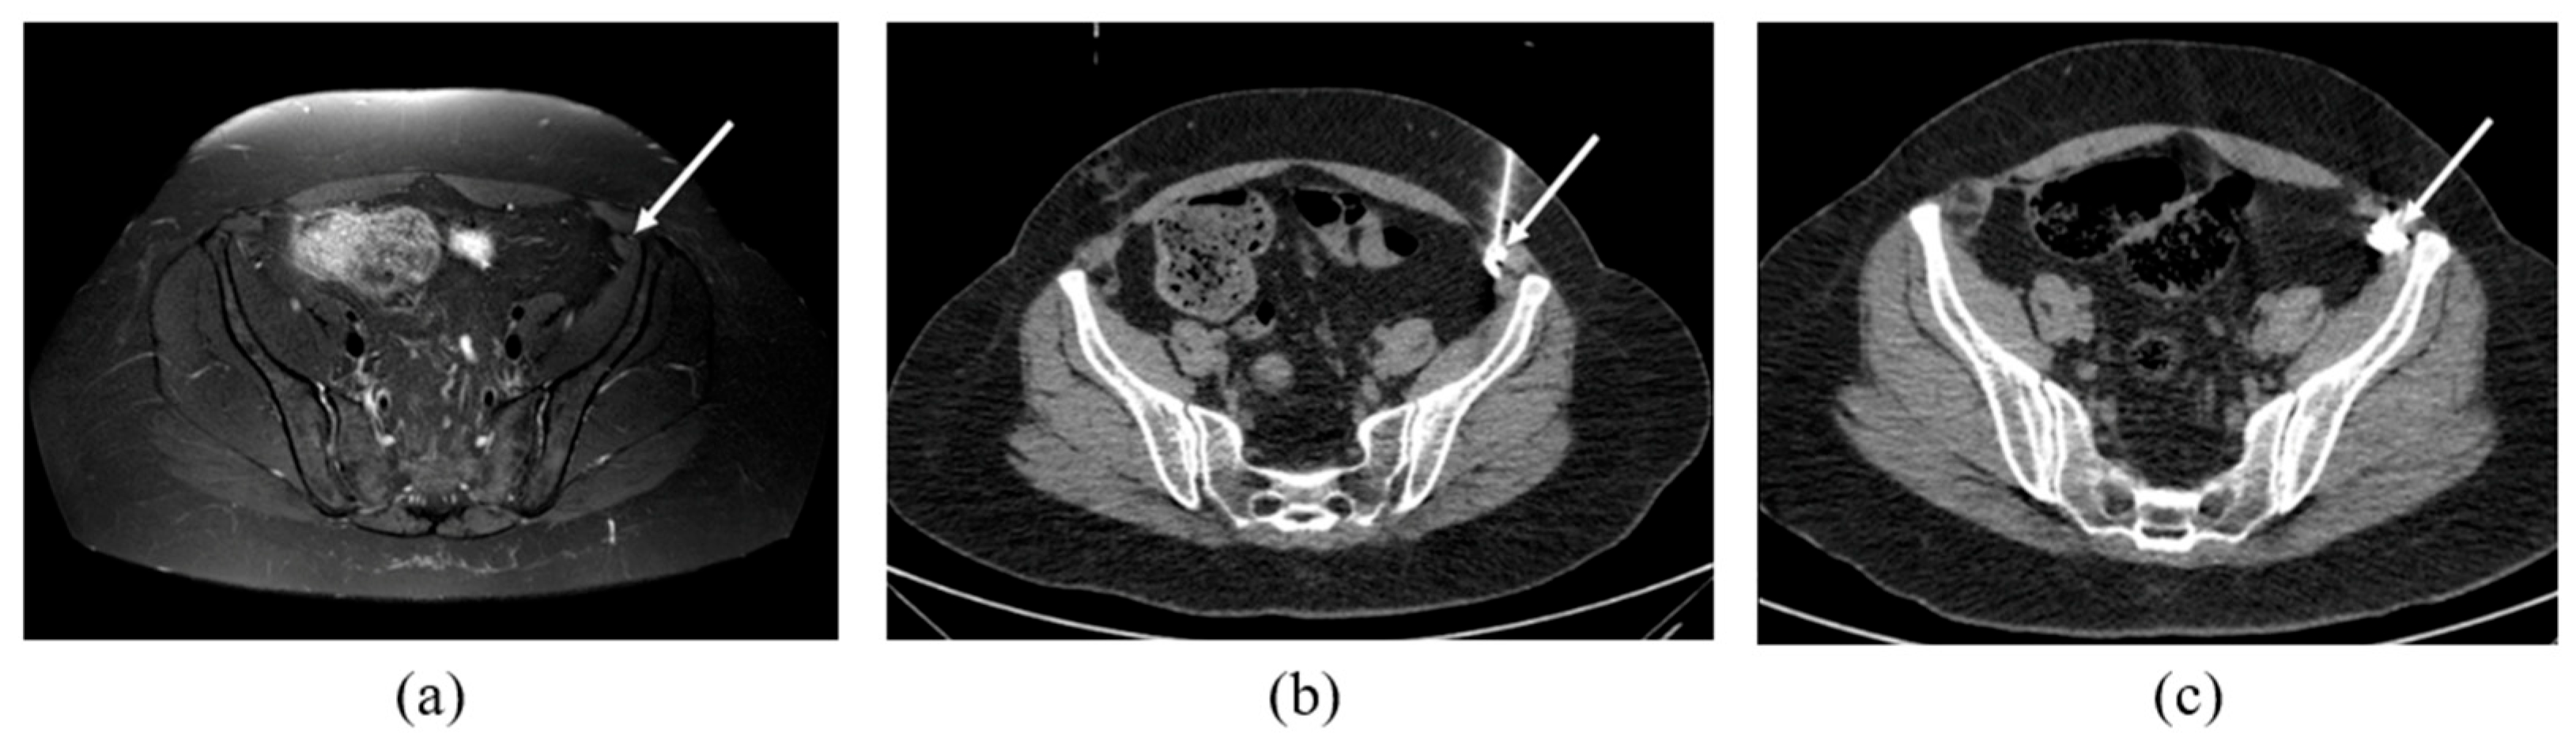

2.2. CT-Guided Procedures